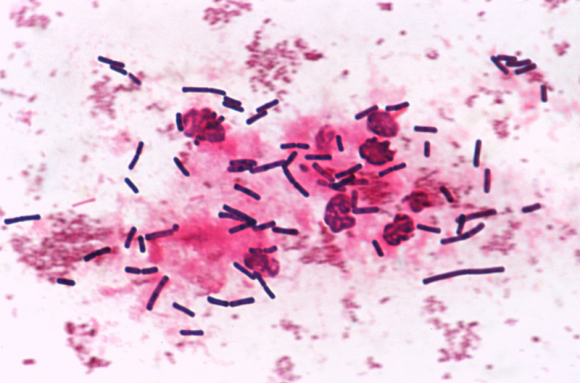

La parasitologie est la science qui étudie les organismes parasites (animaux, végétaux, champignons ou fungi), ainsi que les maladies qu'ils génèrent chez l'Homme, les animaux ou les plantes.

Les parasites internes, ou endoparasites, vivent à l'intérieur du corps de leur hôte, et y prélèvent des éléments nutritifs, tout en profitant d'un environnement (biotope) propice à leur développement. L'organisme parasite présente parfois une modification importante de sa morphologie et de sa physiologie par rapport aux autres espèces de son groupe taxonomique.